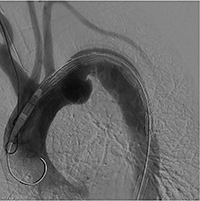

■胸部大動脈瘤におけるステントグラフト内挿術

TEVAR術中画像(2) |